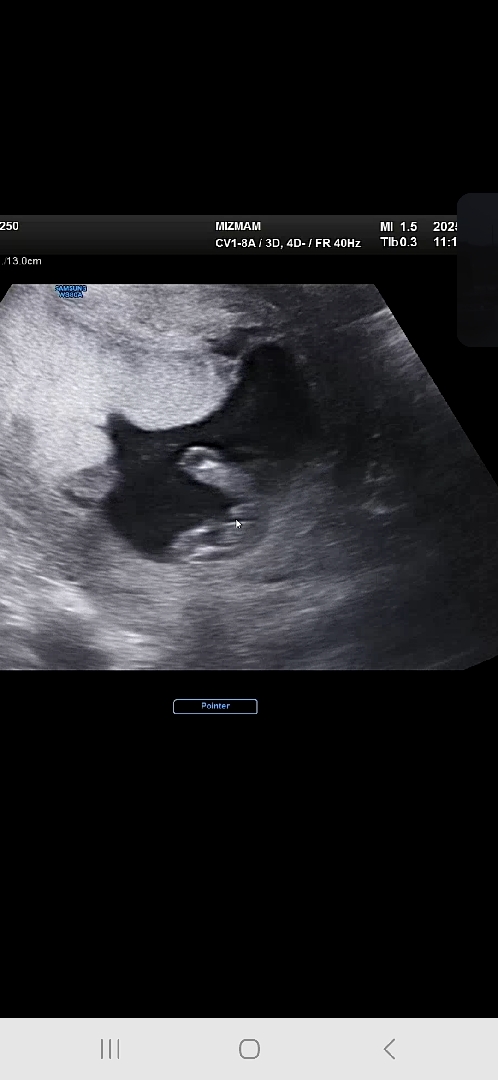

13주 6일에 찍었던건데 아들일까요ㅋㅋ

이 정도면.. 반전 없겠죠..?ㅋㅋㅋ

이정도면.... 확정이네요 ㅎㅎ